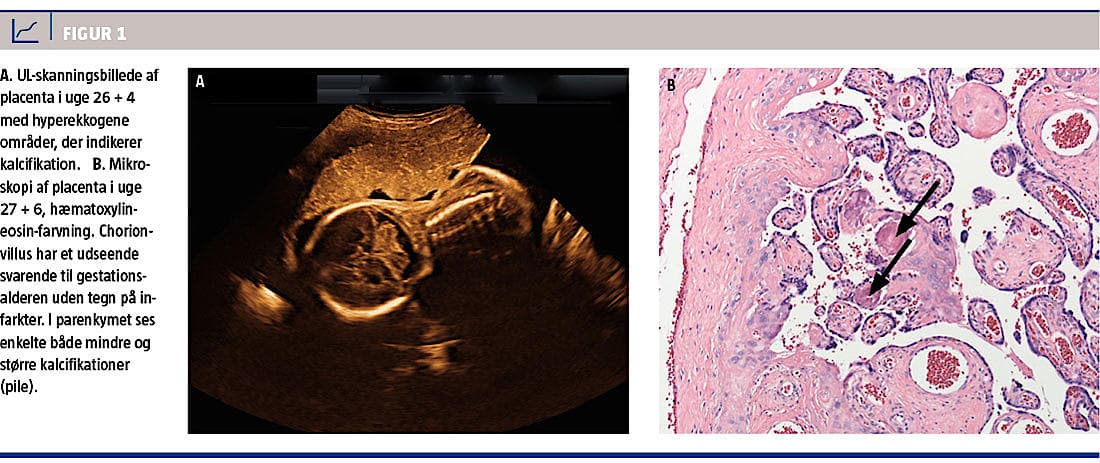

I uge 24 + 5 fandtes føtal vækstretardering med en vægtafvigelse på –18% og –5% hos hhv. gemellus A og B med normale flow i a. umbilicalis og normal fostervandsmængde. I uge 26 + 4 var vægtafvigelsen –17% og –11% hos hhv. gemellus A og B, med normale flow og fostervandsmængde. I placenta forekom der talrige hyperekkogene områder, hvilket var foreneligt med forkalkninger (Figur 1A). Patienten blev i uge 26 behandlet med betamethason pga. vaginalblødning og risiko for snarlig forløsning.

Begge tvillinger var respiratorisk påvirkede fra starten og måtte intuberes. Hos begge udvikledes der store grad IV-intraventrikulære blødninger. Tvilling A afgik ved døden, og tvilling B fik hydrocefalus. Mikroskopi af placenta viste kalcifikationer i parenkymet (Figur 1B).